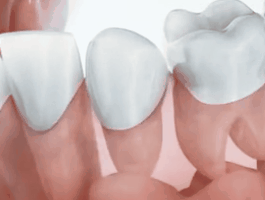

因为从小吃够了牙齿的苦,所以就像公号里很早和大家分享牙齿科普知识一样,我对OK口腔健康一直是比较重视的。一方面因为刷牙开始得很早、刷的时候也保质保量,一方面他可能遗传了爷爷良好的牙齿基因,所以乳牙虽然也有黑色素沉淀,但没有任何蛀牙。可就是没想到,OK换牙时出现了双排牙(当时没拍)。我在网上找了下面这张图,就是类似这种情况,乳牙还在原位,但是下面恒牙已经冒出头来了,看起来还挺滑稽。

正常情况下,恒牙是长在乳牙下面的。恒牙在萌生过程中,直接压迫乳牙根,使乳牙根渐渐吸收,变得越来越短,直至完全消失。于是乳牙便开始脱落,恒牙逐渐长出。

△换牙过程